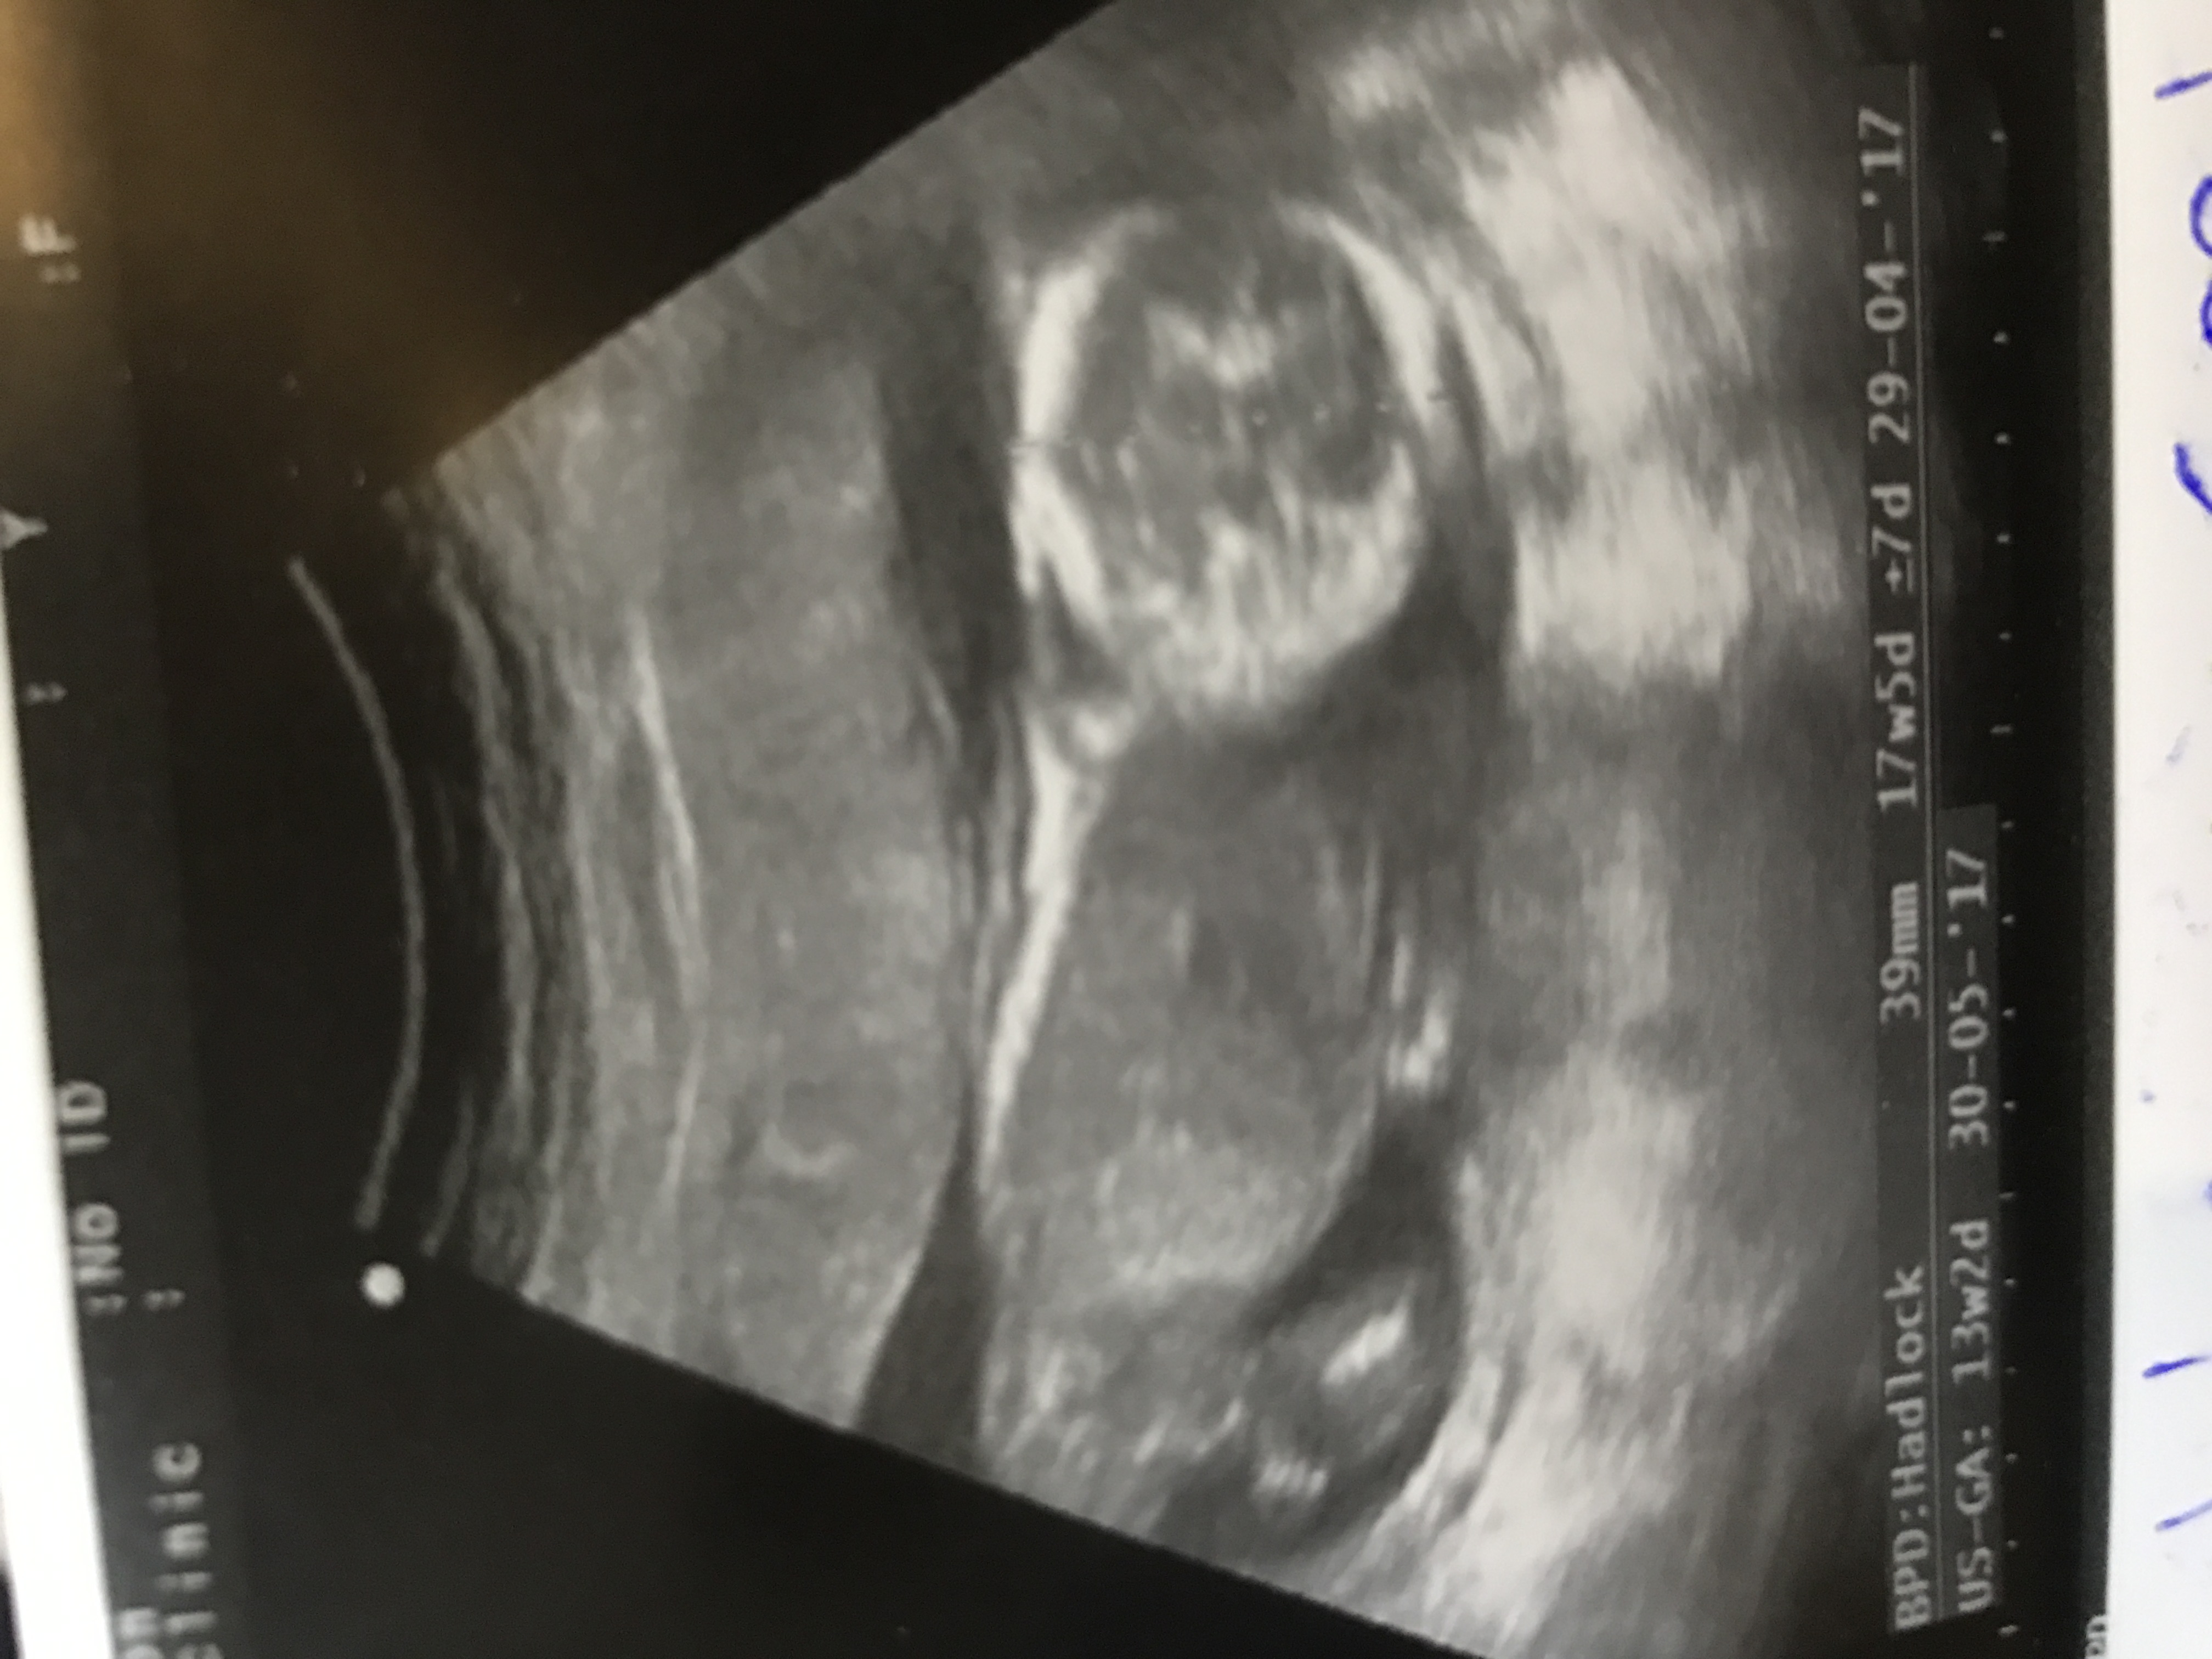

the tech couldnt know because she couldnt take the potty shot .. thank you this is a 17 weeks ultrasound